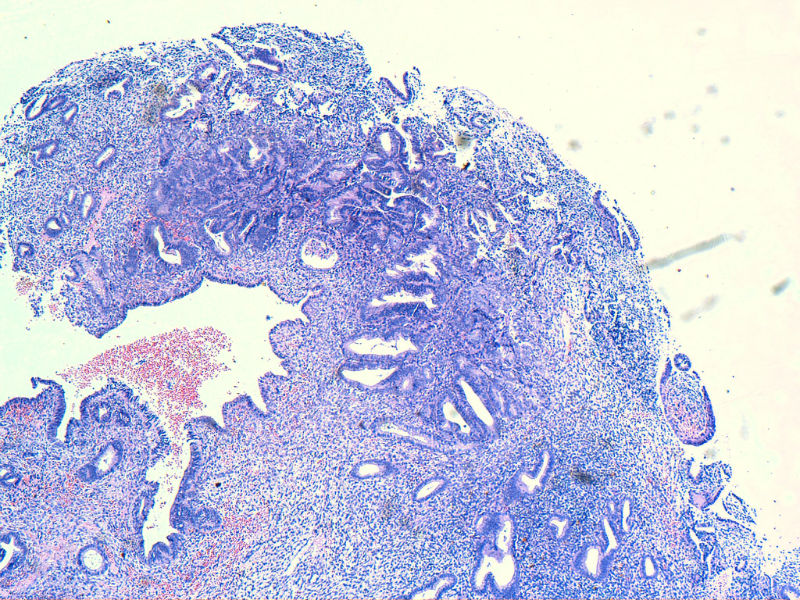

子宫内膜EIN?

子宫内膜EIN?图1

名称:图1

图13是做为正常对照的,图7、8、9、12显示的核大小不一,空泡状,形状不规则。女,48岁,宫血半年